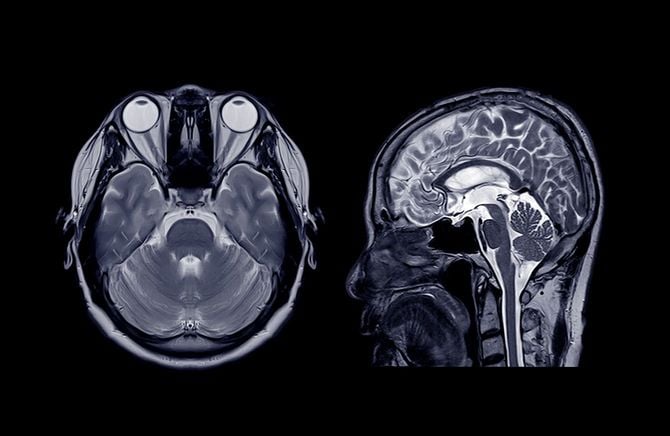

2014年9月。人工頭蓋骨を入れる手術を受けた。夫は、5月の開頭手術後に脳がむくんで脳幹が圧迫されたために、緊急で「開頭外滅圧術」を行い、いったん頭蓋骨を外したままの状態にしていた。

そろそろ人工頭蓋骨に、ということになったのだが、1カ月たっても傷口がうまくつかず、感染を起こしてしまったため、やむなく人工頭蓋骨を外す手術を行った。

またあるとき、夫は「2階に上がるスイッチ」が入った。以前は2階に寝室があったからだ。そこで白井さんは、娘たちが小さい頃使っていたバリケードを階段の前に設置。夫は頭蓋骨がないため、頭をぶつけたりしたら即死だ。白井さんはヘルメット兼サポーターのような保護帽子をオーダー。夫に被らせ、薄い膜だけで脳が半ばむき出しのような状態になっていた部分を覆った。